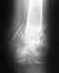

Здравствуйте,подскажите пожалуйста как описывать перелом малоберцовой кости.перелом оскольчатый, в нижней трети кости.